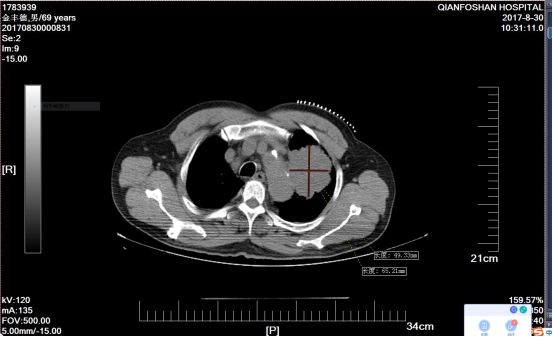

李老伯术前肿瘤CT影像图经过李老伯的子女辗转打听,在确诊一周后李老伯便来到山一大一附院。“肺鳞癌又称肺鳞状上皮细胞癌,是我国最常见的肺癌类型之一,多见于老年男性,与吸烟有密切关系。”医院肿瘤微创科主任医师刘元水表示,众所周知,手术、放疗、化疗被称为癌症治疗的三板斧。因为发现较晚,患者左肺部肿瘤达6.4cm x 5.3cm并侵犯了主动脉弓,已经失去了手术指征,且肺鳞癌对放疗、化疗不敏感,治疗效果有限。